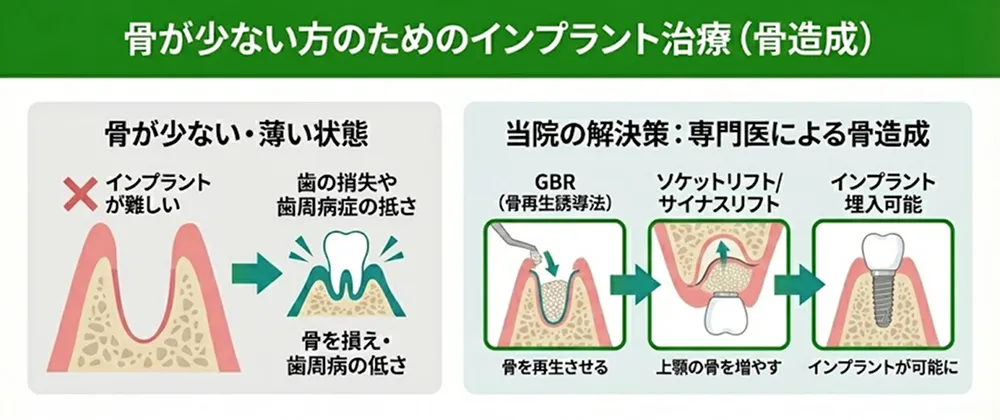

骨が少ない/薄い方

インプラントを埋入するためには、十分な量の顎の骨が必要です。しかし、歯を失ってから時間が経過していたり、歯周病の影響で骨が痩せてしまっている方も少なくありません。

当院にはGBR、ソケットリフト、サイナスリフトなどの骨造成技術を持つ専門医が在籍しており、骨が少ない・薄いという理由で断られた方も多く治療しています。

※すべてのケースでインプラント治療が可能になるわけではありません。